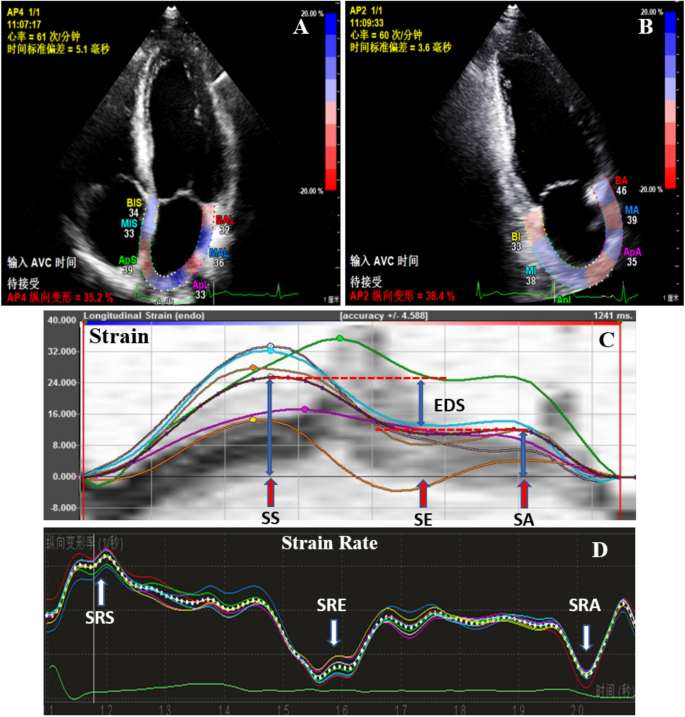

For 2D-STE, echocardiographic images were stored at 60–100 frames per second in three cardiac cycles. The strain and strain rate were measured at apical 4- (AP4) and 2-chamber (AP2) views respectively using Qlab10.5 workstation. Initially, the endocardial border of the LA was manually traced in aCMQ mode at end ventricular systole, the epicardial borders of the LA wall were automatically defined through software, and the width was manually adjusted so that the tracking area covered the full thickness of the myocardium. After the adjustment and confirmation of these traced borders, the software automatically calculated and displayed the results (Fig. 1). In patients with adequate image quality, six segments were analyzed. The left atrial global longitudinal strain (LA-GLS) was read on the strain curves of AP4 and AP2 respectively (Fig. 1A,B). The longitudinal LA strain curve had a positive systolic peak (SS), an early diastolic plateau (SE), and a late diastolic peak (SA) (Fig. 1C). The longitudinal LA strain rate curve had a positive systolic peak (SRS), an early negative peak at early diastole (SRE), and a late negative peak at late diastole (SRA) (Fig. 1D). SS and SRS represented the LA reservoir function, EDS (= SS − SA) and SRE reflected the LA conduit, and SA and SRA were the indices of the LA booster function. The value was the average of the AP4 and AP2 measurements, presenting as LA longitudinal average strain (LA-mGLS), and average strain rate: LA-mSRS, LA-mSRE and LA-mSRA. All the image and strain analyses were done by a single expert echocardiologist.

(A) Apical 4 chamber view; (B) Apical 2 chamber view; (C) Strain curve: The longitudinal LA strain curve had a positive systolic peak (SS), an early diastolic plateau (SE), and a late diastolic peak (SA); (D) Strain rate curve: the longitudinal LA strain rate curve had a positive systolic peak (SRS), an early negative peak at early diastole (SRE), and a late negative peak at late diastole (SRA). SS and SRS represented the LA reservoir function, EDS (= SS − SA) and SRE reflected the LA conduit, and SA and SRA were the indices of the LA booster function.